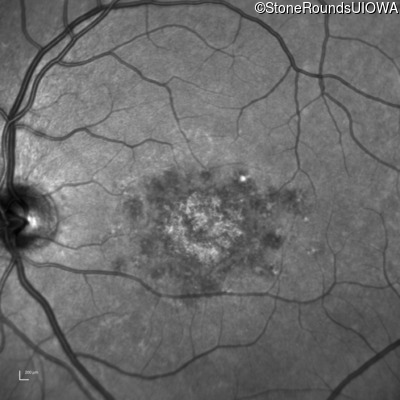

Blue Autofluorescence - Left - 20/200 -2 sc

Exemplar